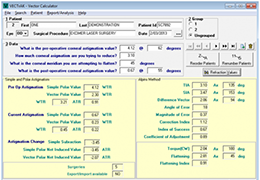

ANYTHINK 经导管主动脉瓣膜置换术分析系统